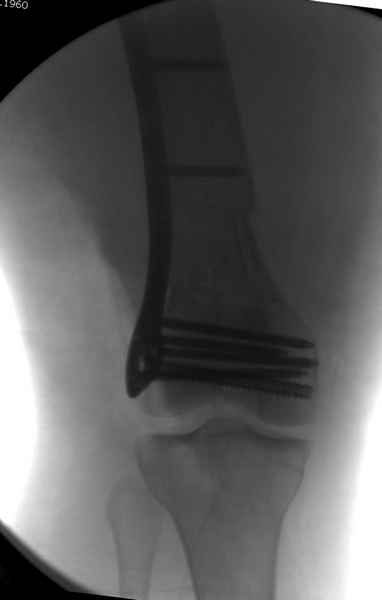

Имя     : distal femur.jpg

Тип     : image/jpeg

Размер  : 14488 байтов

Описание: отсутствует

Url     : http://weborto.net:8080/pipermail/ortho/attachments/20081001/5646c87e/attachment-0011.jpg